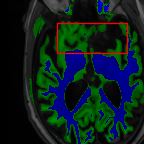

Sparsity LI 2D CNN 3D CNN Ours GT

4 Refer to caption (a) 0.6787/0.7972 Refer to caption (b) 0.8143/0.8776 Refer to caption (c) 0.8190/0.8714 Refer to caption (d) 0.8664/0.9085 Refer to caption (e) GM/WM

Refer to caption (f) 0.6808/0.7161 Refer to caption (g) 0.8103/0.8631 Refer to caption (h) 0.7950/0.8606 Refer to caption (i) 0.8598/0.9115 Refer to caption (j) GM/WM

8 Refer to caption (k) 0.5139/0.7240 Refer to caption (l) 0.6619/0.8224 Refer to caption (m) 0.6878/0.8584 Refer to caption (n) 0.7798/0.8853 Refer to caption (o) GM/WM

Refer to caption (p) 0.5910/0.6947 Refer to caption (q) 0.6516/0.8021 Refer to caption (r) 0.6507/0.8186 Refer to caption (s) 0.7471/0.8540 Refer to caption (t) GM/WM

Figure 6: Visual comparison of gray matter (Green)/white matter (Blue) segmentation over different methods, with respective DICE scores listed under the images.

In Fig. 6, we demonstrate the advantage of the proposed method in brain matter segmentation. It is clear that although 2D and 3D CNN generates visually plausible interpolation as presented in Fig. 5, the brain matters are easily misclassified due to incorrect anatomical structures and blurred details.